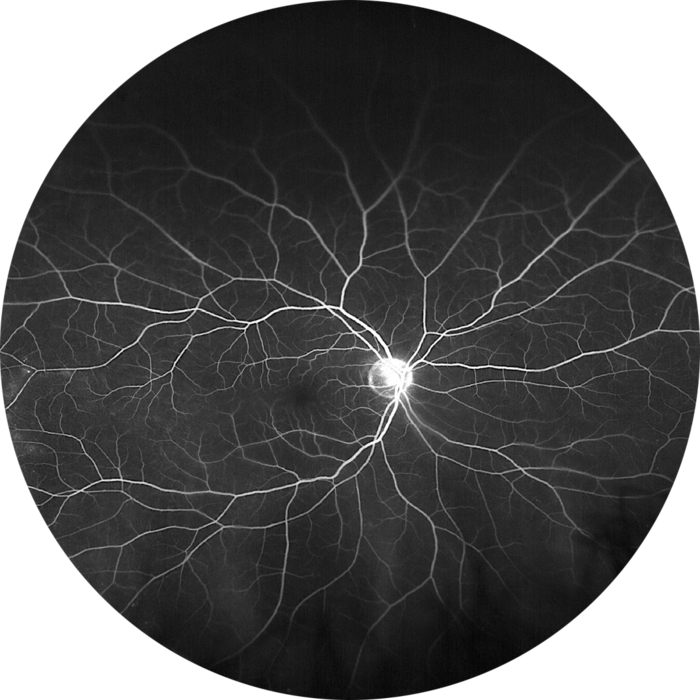

Macular Degeneration

Macular degeneration, a leading cause of vision loss in older adults, affects the macula, the central part of the retina responsible for sharp, central vision. This crucial area of the eye allows us to read, drive, and recognize faces. Understanding the different types, causes, and treatment options is vital for those affected and those seeking to prevent or manage this condition.Macular degeneration isn’t a single entity; it encompasses several forms, each with its own characteristics.

Macular degeneration significantly impacts vision, affecting the ability to perform daily tasks. Central vision loss makes reading, driving, and recognizing faces challenging. Individuals may experience distorted or blurred central vision, leading to difficulties with tasks requiring precise detail. The impact extends to social interactions, professional life, and overall quality of life. For example, someone with significant macular degeneration might find it hard to read a menu or recognize a friend’s face.